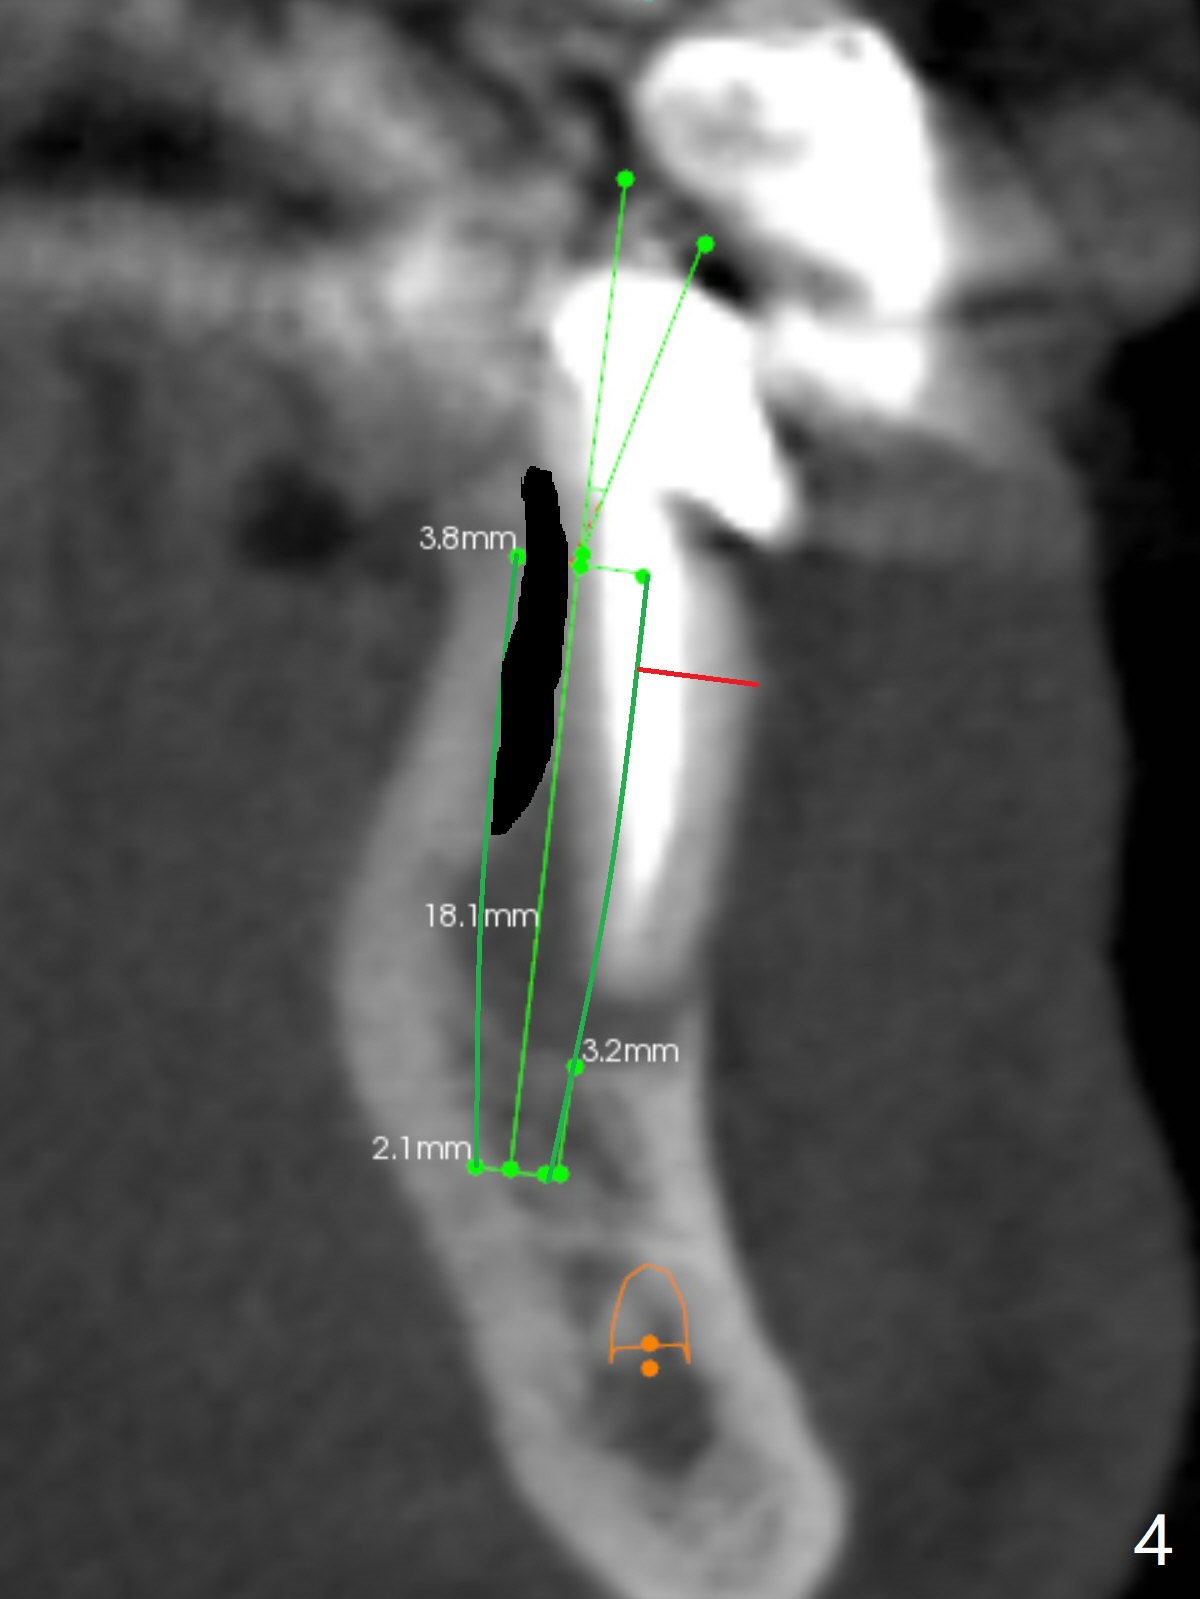

A 61-year-old man has poor dentition (#7 10), requesting extraction of the tooth #22 with root split (Fig.1 *). CT taken 1.5 years earlier (before crown fracture) shows missing buccal plate (Fig.2 B). After extraction, a smallest, longest 2-piece implant (3.8x18 mm) will be chosen to gain ~ 3 mm apical native bone for primary stability; to obtain a 2 mm buccal gap (Fig.3 red line), the implant will be placed as lingual as possible. To achieve the buccal gap, the buccal portion of the lingual plate (Fig.3 L) will be removed (Fig.4 black area) using Lindamann bur. For restoration, a 15 or 25 degree angled abutment may be used (Fig.3,4). If the root is stable, socket shield will be performed.